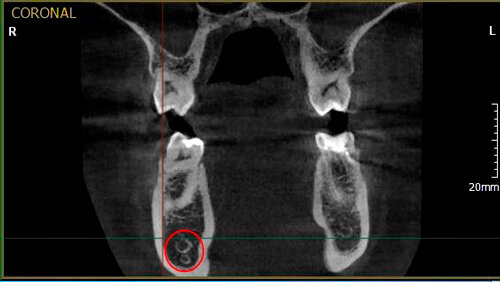

Диагностика повреждения нижнего альвеолярного нерва при дентальной имплантации посредством конусно-лучевой компьютерной томограф

Резюме Исход потери чувствительности временного или постоянного характера при повреждении нижнего альвеолярного нерва после хирургического этапа дентальной имплантации не очевиден. Изменения чувствительности могут выражаться различными симптомами. Сравнительный анализ различных методов лучевой диагностики установил, что использование конусно-лучевой компьютерной томографии при данном виде осложнении влияет на тактику дальнейшего лечения. Ключевые слова:  Конусно-лучевая компьютерная томография,...